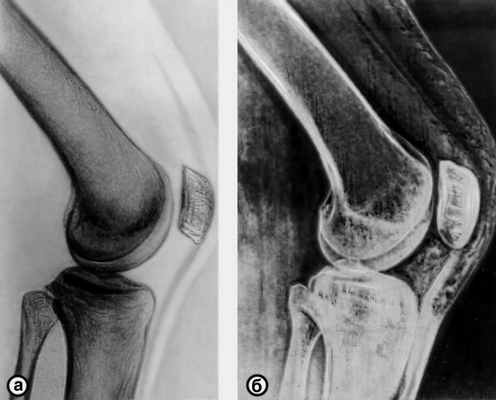

Электрорентгенография имеет ряд важных отличий от рентгенографии (Рентгенография). В частности, при Э. отмечается так называемый краевой эффект — более интенсивное отложение порошка на границе участков с различными потенциалами, что обеспечивает четкость контуров тени, высокую контрастность и некоторое увеличение изображения. Все это создает впечатление объемности деталей и повышает диагностические возможности метода. При исследовании мягких тканей удается получить изображение кожи, подкожной клетчатки, мышц, связок, что позволяет выявлять очаги воспаления, кровоизлияния, кисты. Метод позволяет одновременно получить изображение тканей, различающихся по плотности и толщине. Так, при исследовании суставов наряду с суставными концами костей определяются элементы связочного аппарата, сухожилия, мышцы (рис.).

электрорентгенограмма (б) коленного сустава в норме (боковая проекция)">